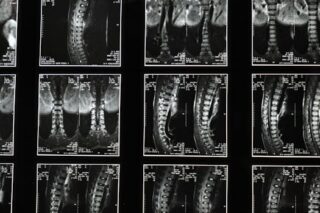

Diagnosis typically involves a combination of a physical examination, patient history, and imaging studies such as X-rays or MRIs. These assessments help identify the presence and extent of bony growths and their impact on the spinal structure.